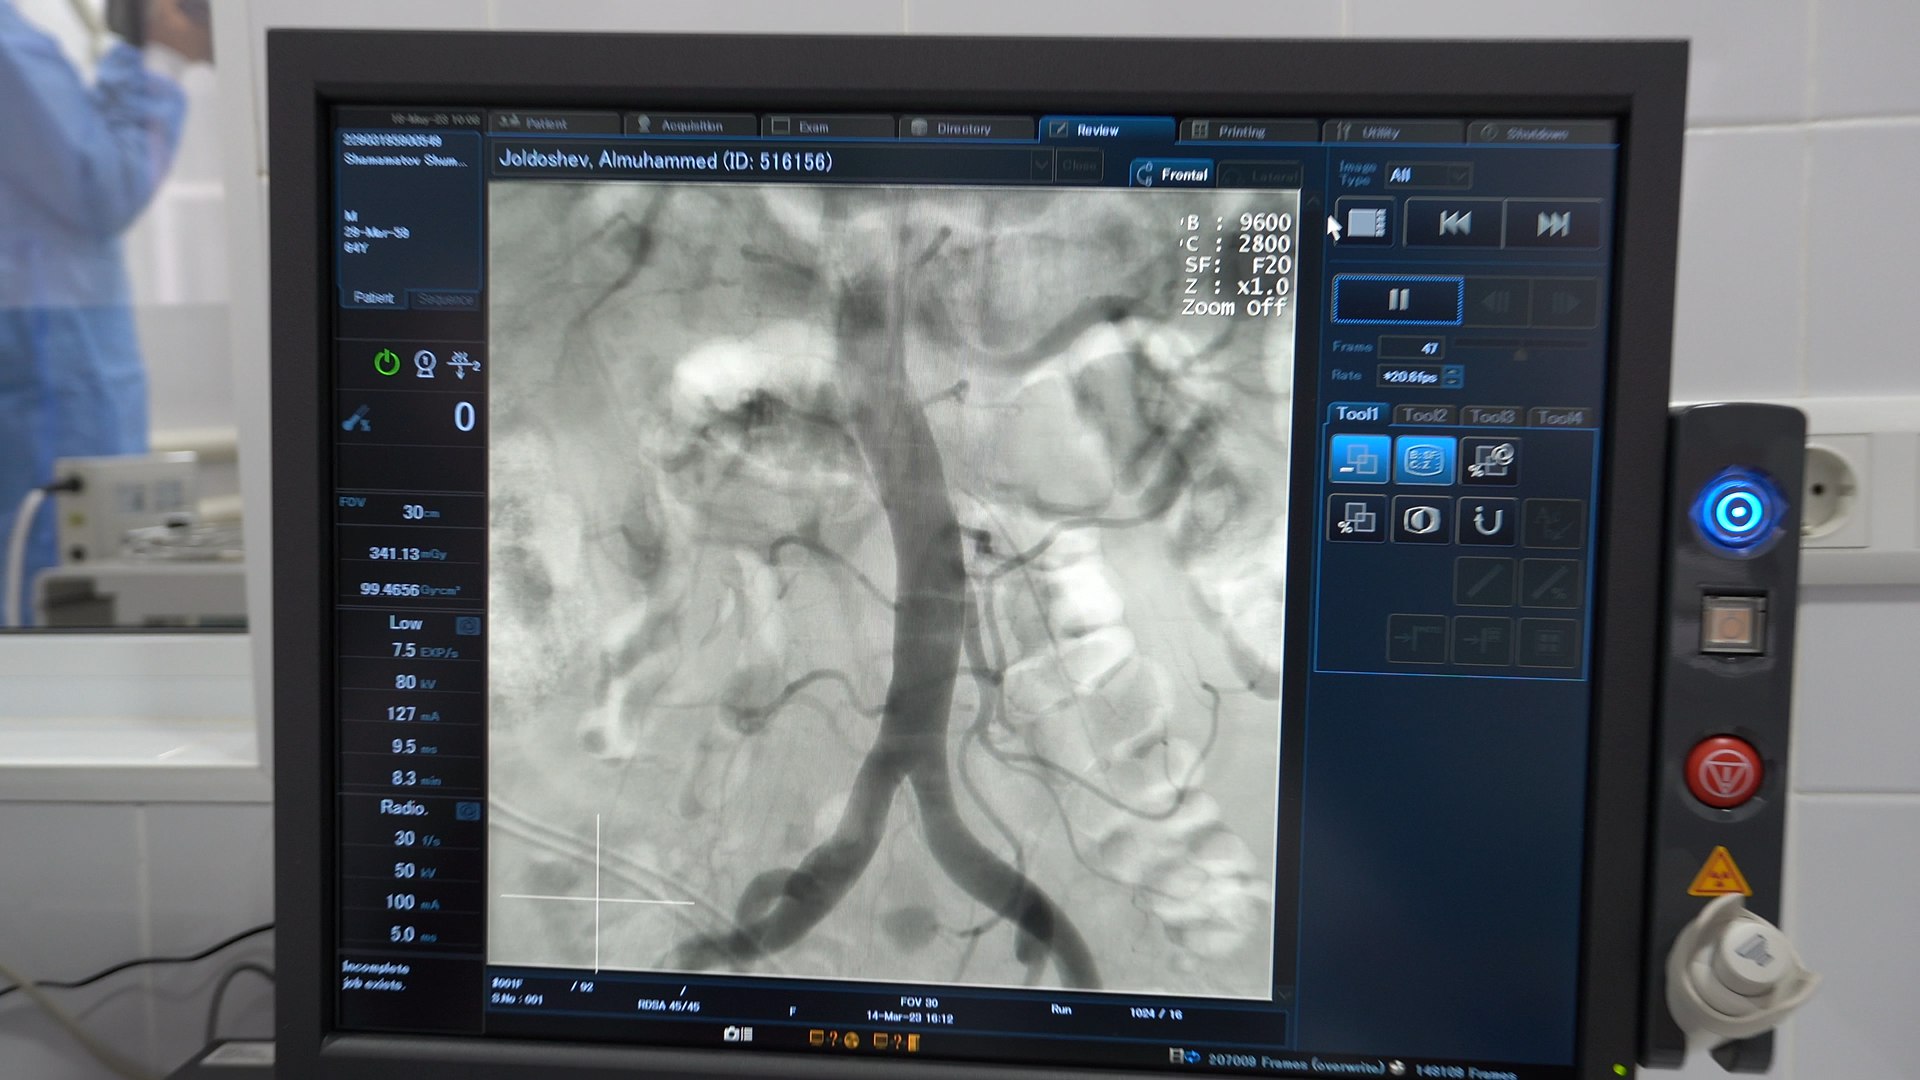

Новый комплекс включает в себя передовые технологии: подвижную С-образную дугу, ангиографический стол, генератор и излучатель, детектор, цифровую многозадачную систему для сбора, обработки и хранения данных, а также мониторы и модули управления.

«Оборудование может служить инструментом для визуализации и навигации хирурга внутри тела пациента. Таким образом, ангиографический комплекс открывает новые возможности для выполнения сложных вмешательств и хирургических операций с высокой точностью и безопасностью», — отметили в ведомстве.